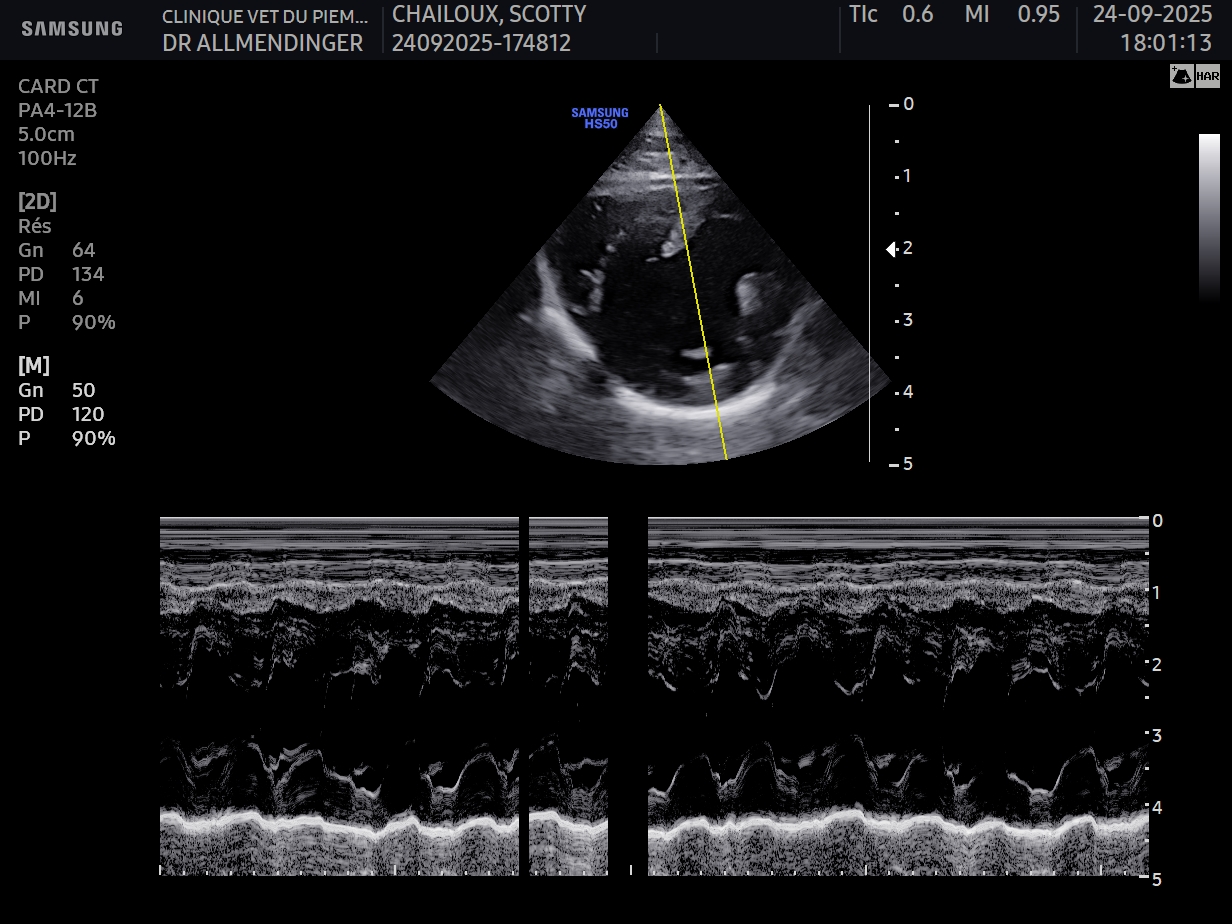

Exploration cas clinique : syncope chez le chat

- Connaître les outils permettant la confirmation d’une syncope cardiogénique chez un

chat - Connaître les causes d’une syncope cardiogénique chez le chat

- Connaitre les traitements possibles lors de syncope cardiogénique chez le chat